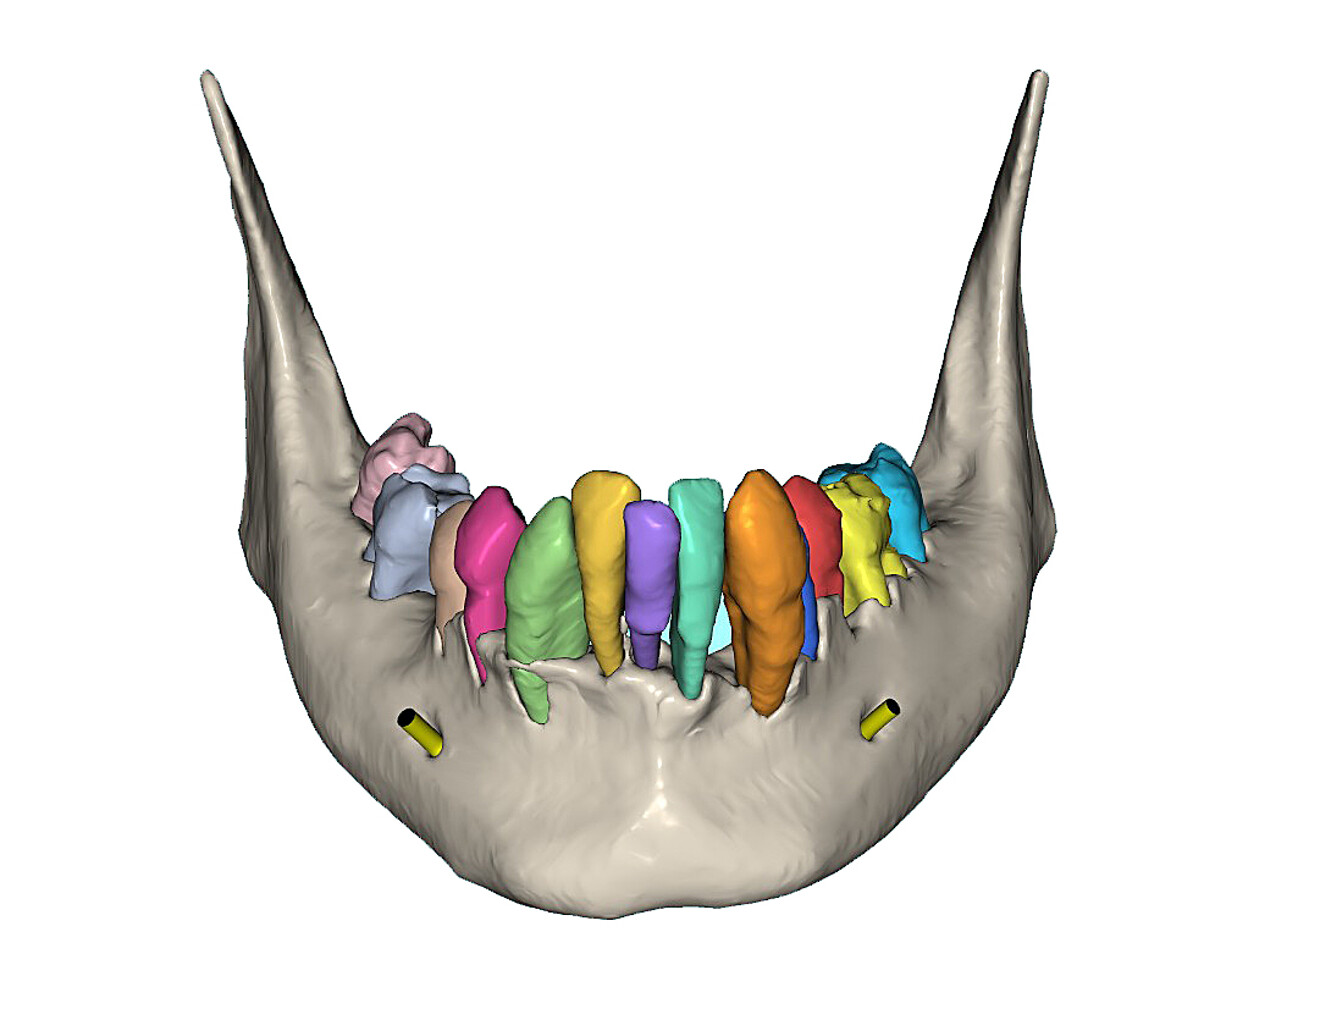

The mandibular arch followed a similar surgical protocol utilising a bone-borne surgical guide after tooth extraction and bone reduction. The advanced bone and tooth segmentation illustrated the severe bone loss almost to the apex of many of the mandibular roots (Fig. 13a). Using selective transparency, the roots and bone could be closely evaluated (Fig. 13b). 3D volumetric reconstruction simulating the post-extraction bone helped provide a unique view of the mandibular bony anatomy (Fig. 14a) and aided in finalising the location of each implant (Fig. 14b).

Fig. 14a: Occlusal view of the simulated extraction sockets in the mandibular bone.

Fig. 14b: Simulation of parallel implants in the mandible with yellow abutment projections

In accordance with my recommendations, the simulated bone reduction was calculated only after the implant positions had been confirmed. Selective transparency was also an important feature when assessing the proximity to the bilateral mental foramina and a determinant of the vertical positioning of the implants (Fig. 15a). Once the implant positions had been confirmed, a dual-purpose bone-borne guide was designed (Fig. 15b). The first purpose was to transfer the planned bone reduction to the buccal aspect of the mandible and the second was to guide osteotomy through advanced bone segmentation.